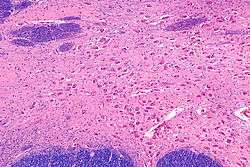

![]() Intermediate magnification micrograph of the nucleus basalis (of Meynert). LFB-HE stain. | |

NBM - very high magnification.